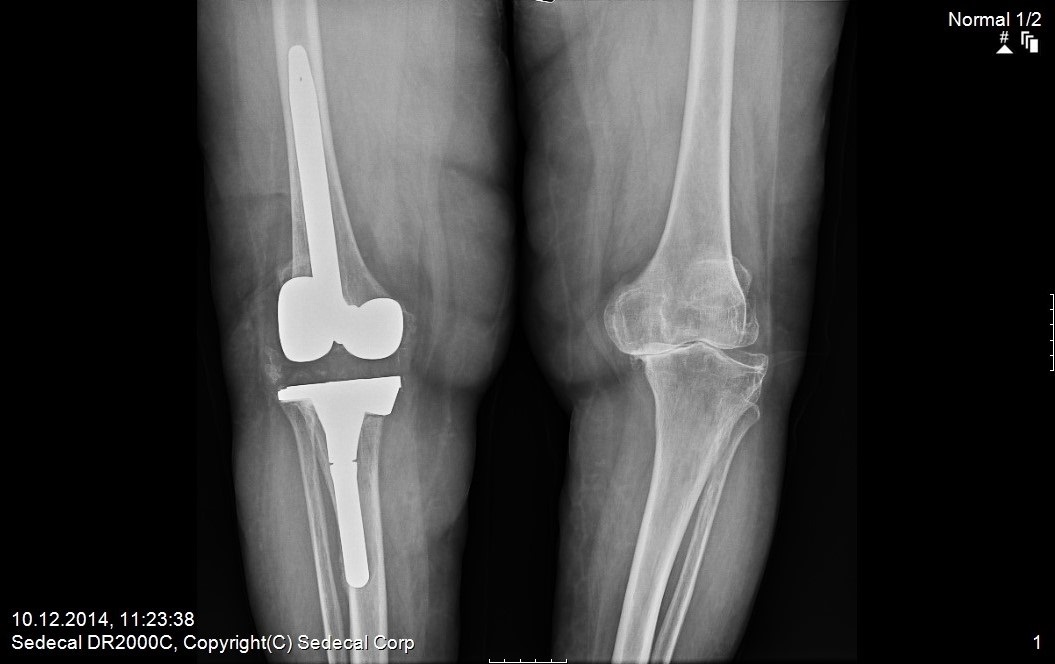

3. kez protez değişimi (menteşeli diz protezi)

ameliyat sonrası 1

ameliyat öncesi 1